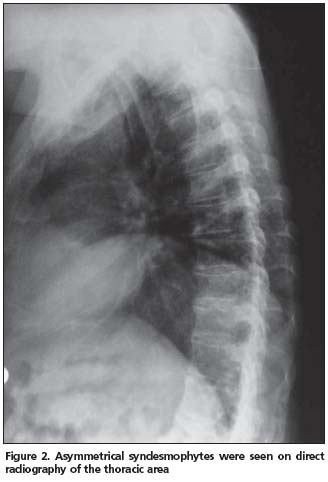

Anterior longitudinal ligament calcification, fusion of multiple facet joints and atypical syndesmophytes were found on cervical spine X-rays (Figure 1) and coarse, asymmetrical syndesmophytes were seen on thoracic (Figure 2) and lumbar spine (Figure 3) X-rays. No abnormalities suggesting PsA or gout were seen on hand and foot radiographs. The magnetic resonance imaging (MRI) of the sacroiliac joint and computerized tomography (CT) of atlanto-axial joint were normal.

PsSpA is observed in 5% of the PsA patients and may be clinically confused with AS[12]. The clinical characteristics of our case also resembled AS. An inflammatory type of low back pain was present and chest expansion was 2 cm. X-rays revealed a predominance of axial involvement. However, a normal sacroiliac joint MRI and lack of a typical syndesmophyte appearance made the AS diagnosis unlikely.